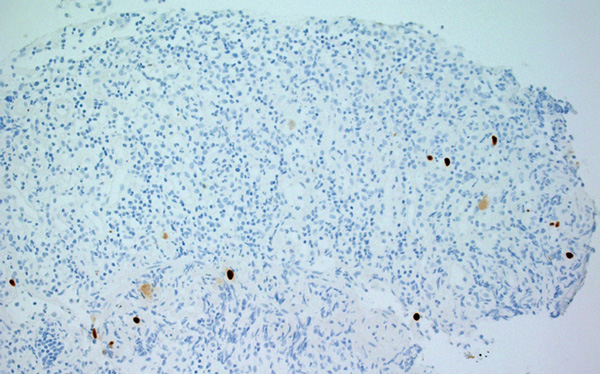

A 32-year-old Indigenous man from a remote Western Australian community presented with a fever, diffuse papular rash and oral ulceration, and a productive cough of 2 weeks’ duration. He was admitted to the intensive care unit (ICU) for respiratory failure and hypotension. Phenytoin 300 mg daily had been prescribed 3 weeks earlier for alcohol-associated seizures. He remained febrile with persistent respiratory failure, and after 10 days he developed profuse diarrhoea and transient hepatitis. Abdominal imaging results were normal and screening tests for bloodborne infections and autoimmune disease were negative. Colonoscopy showed severely inflamed, oedematous mucosa and confluent ulceration, with histological evidence of widespread mucosal loss and granulation tissue overlying inflamed superficial submucosa with prominent cytomegalovirus (CMV) inclusions (Box 1 and Box 2).